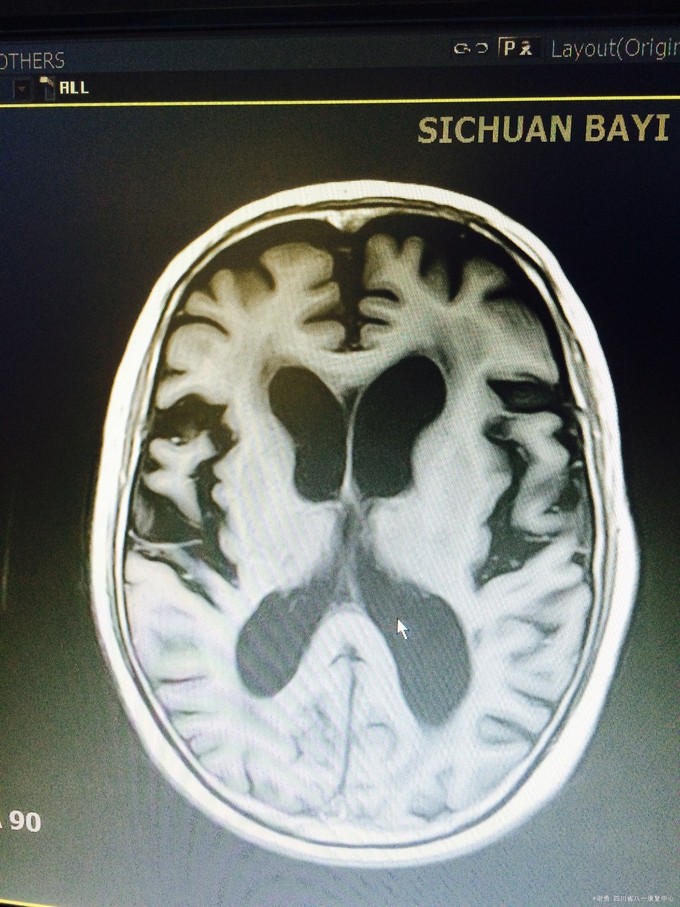

入院查体:血压165/100mmHg,扶入病房,查体合作欠佳,反应迟钝,语言缓慢,记忆力下降,定向力基本正常。四肢肌张力正常。双上肢肌力5级,下肢4级,双下肢病理征阳性;深浅感觉粗测正常。MMSE评分:18分; 辅助检查:血常规,肝肾功、血糖、电解质均正常。头颅MRI 及MRA示:双侧半卵圆中心、脑室旁,基底节区、右侧丘脑、脑干多发缺血灶改变;脑萎缩,脱髓鞘改变;双侧颈内动脉C1-4段边缘欠规则,信号欠均匀。

入院诊断考虑:皮层下动脉硬化性脑病。治疗上主要给以积极改善大脑微循环,控制高血压危险因素,营养神经,改善认知、 记忆功能。治疗半月余,患者症状明显改善,MMSE评分:24分。

出院后口服氨氯地平控制血压,银杏叶、胞二磷胆碱片改善认知,阿司匹林肠溶片卒中二级预防,定期随访!皮层下动脉硬化性脑病又称Binswanger病、进行性皮层下血管性脑病。为老年人在脑动脉硬化基础上,大脑半球白质弥漫性脱髓鞘性脑病。大多发生在50岁以上,在老年人中发病率为1%~5%,男女发病相等。主要累及侧脑室周围、半卵圆中心等皮层下脑深部白质,多为双侧性,常伴有腔隙性脑梗死、脑萎缩。